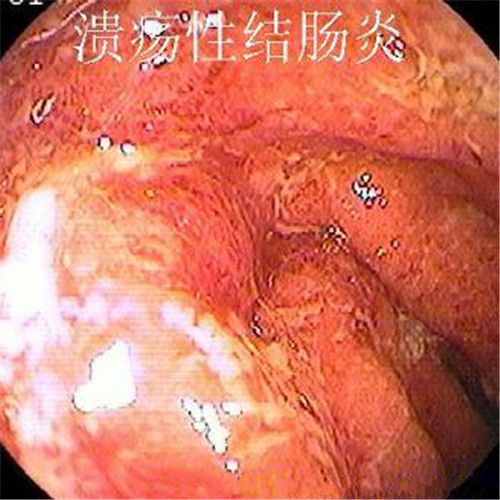

潰瘍性結腸炎圖片

潰瘍性結腸炎重度糜爛